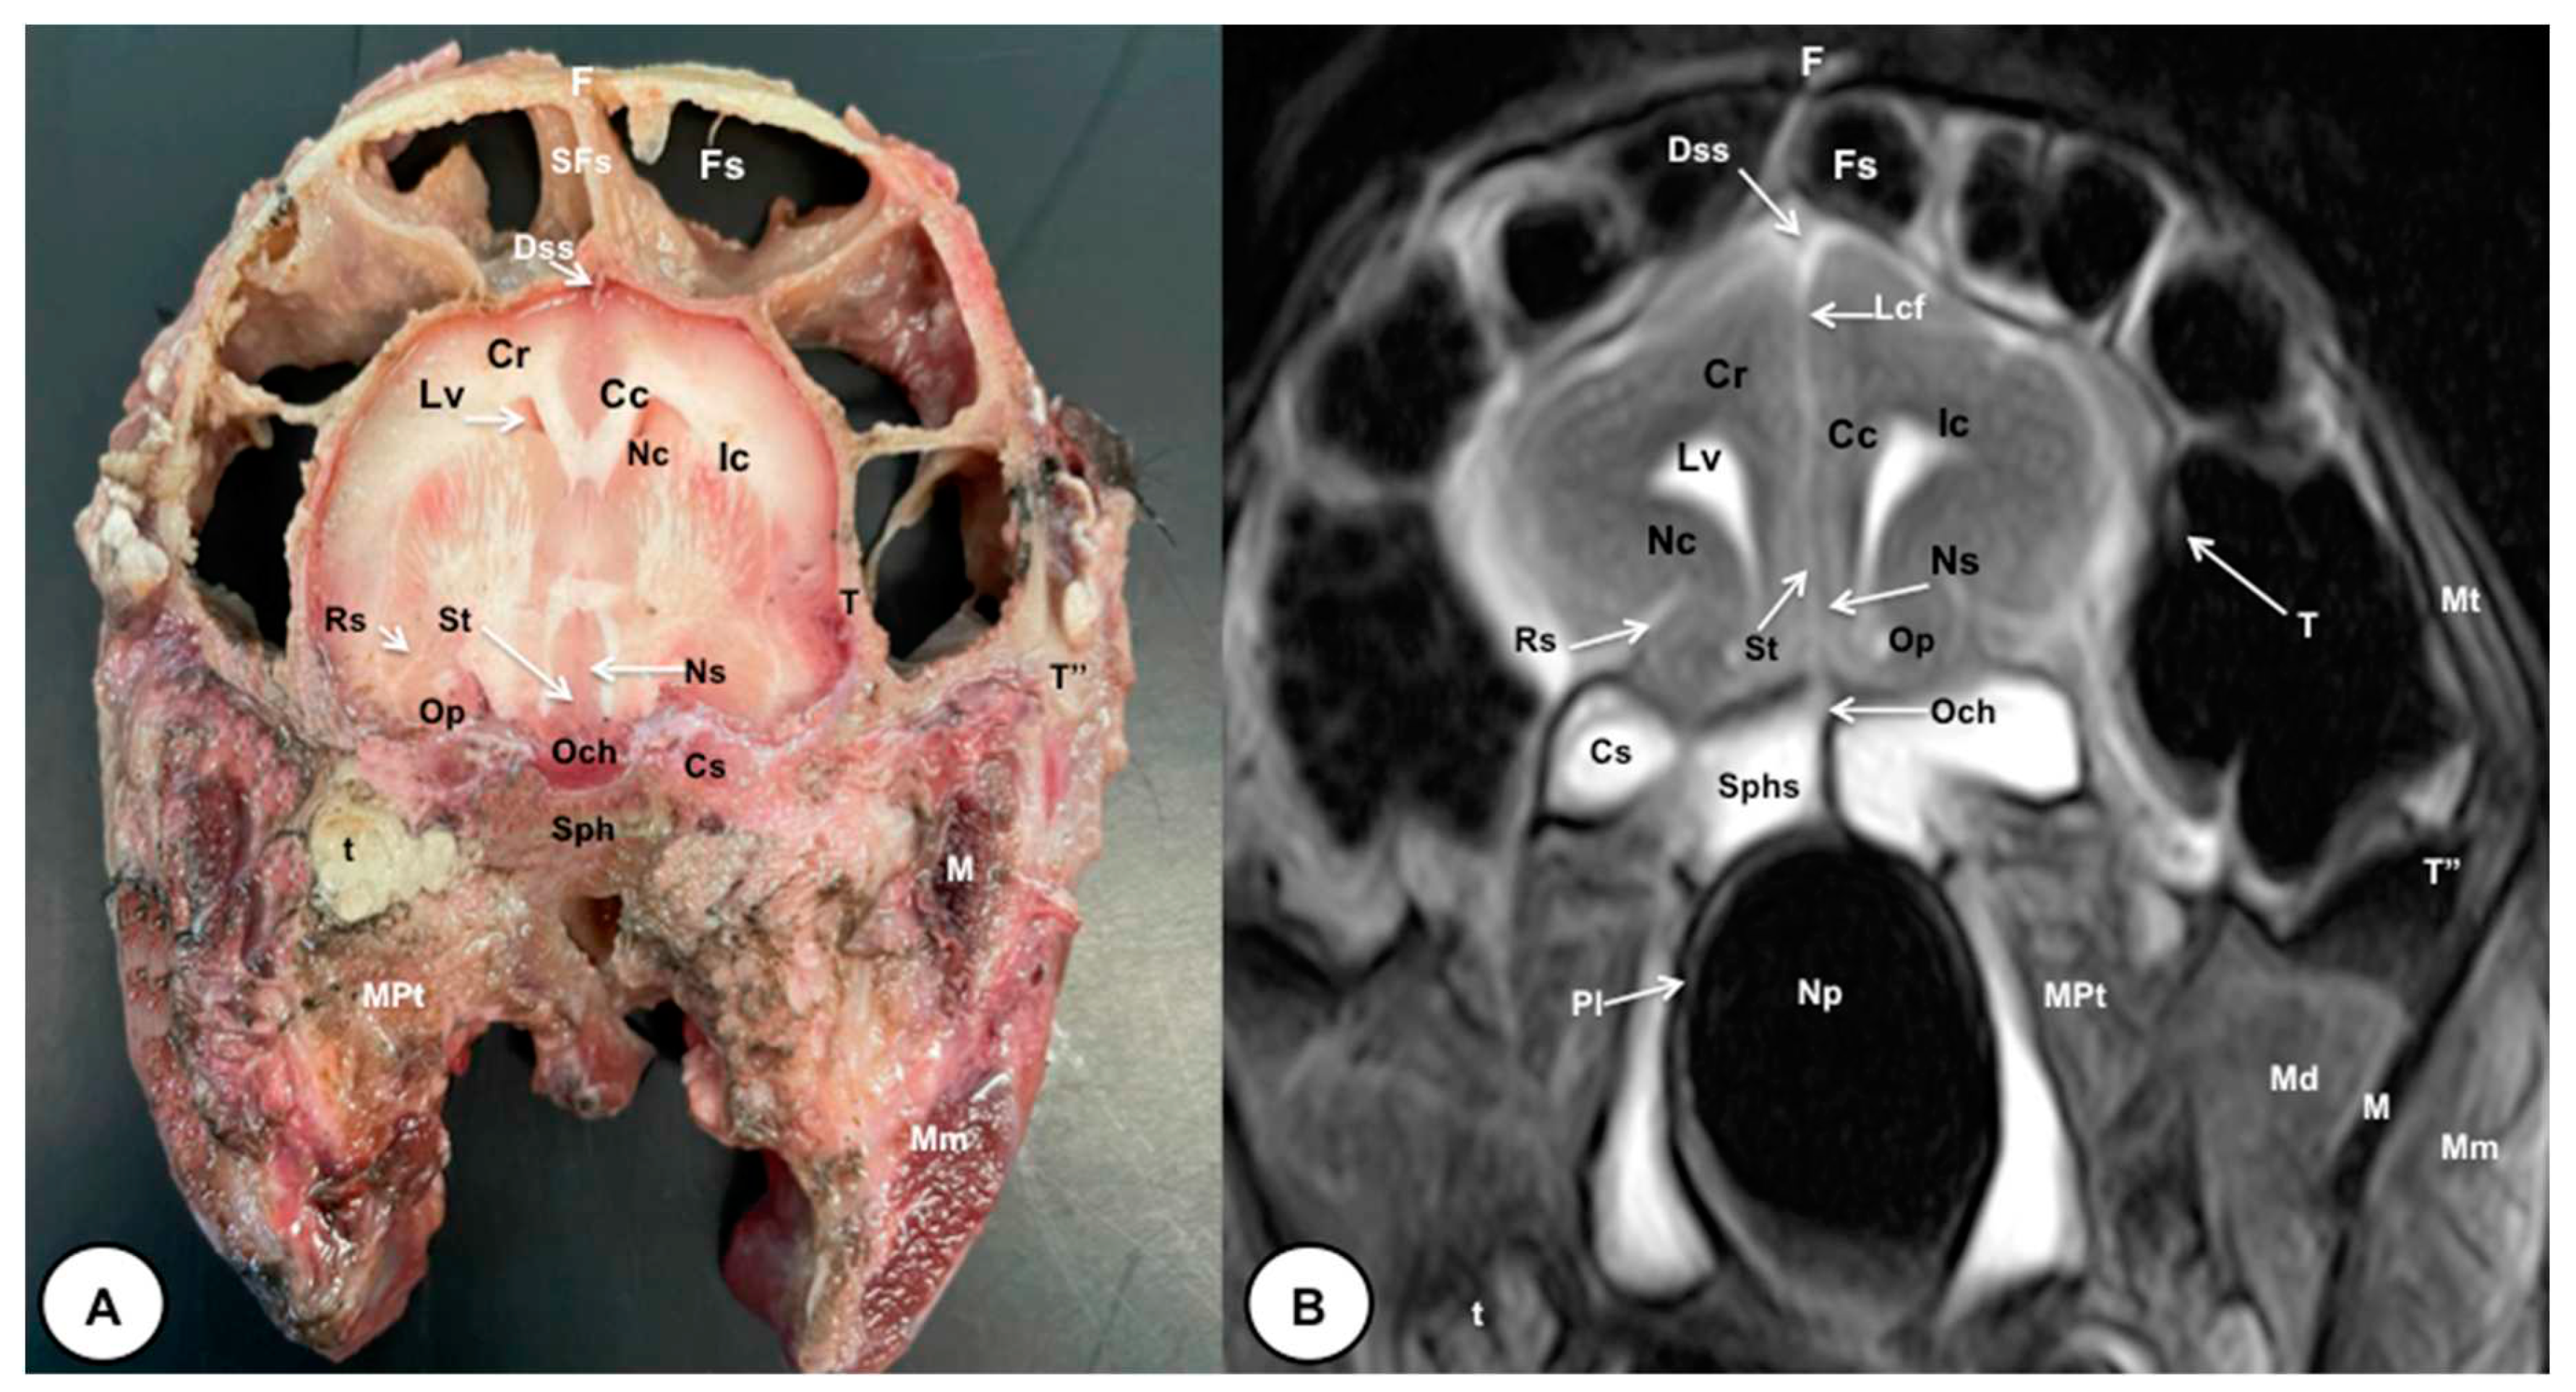

3.1. Anatomical gross-sections

3.2. Magnetic Resonance Imaging (MRI)